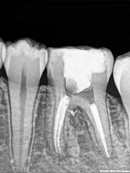

Root Canal Cases